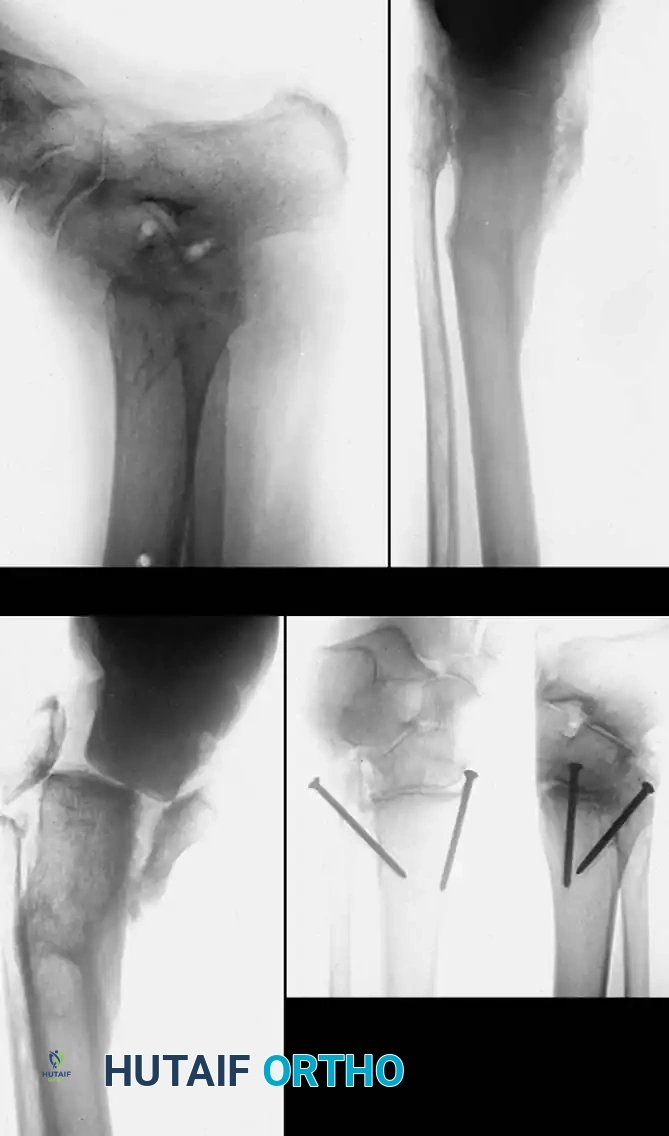

Fig. 1: (A) Malunion of a bimalleolar ankle fracture with preexisting malunion of the distal tibia. (B) Correction achieved; however, arthritis developed. (C and D) Tibiotalar arthrodesis performed using compression clamps, resulting in a painless, stable ankle.

Fig. 6: (A, B) Varus malunion of the distal tibia. (C) Osteotomy of the tibia and fibula with reduction maintained by a circular external fixator. (D, E) Tibial union obtained with normal alignment.